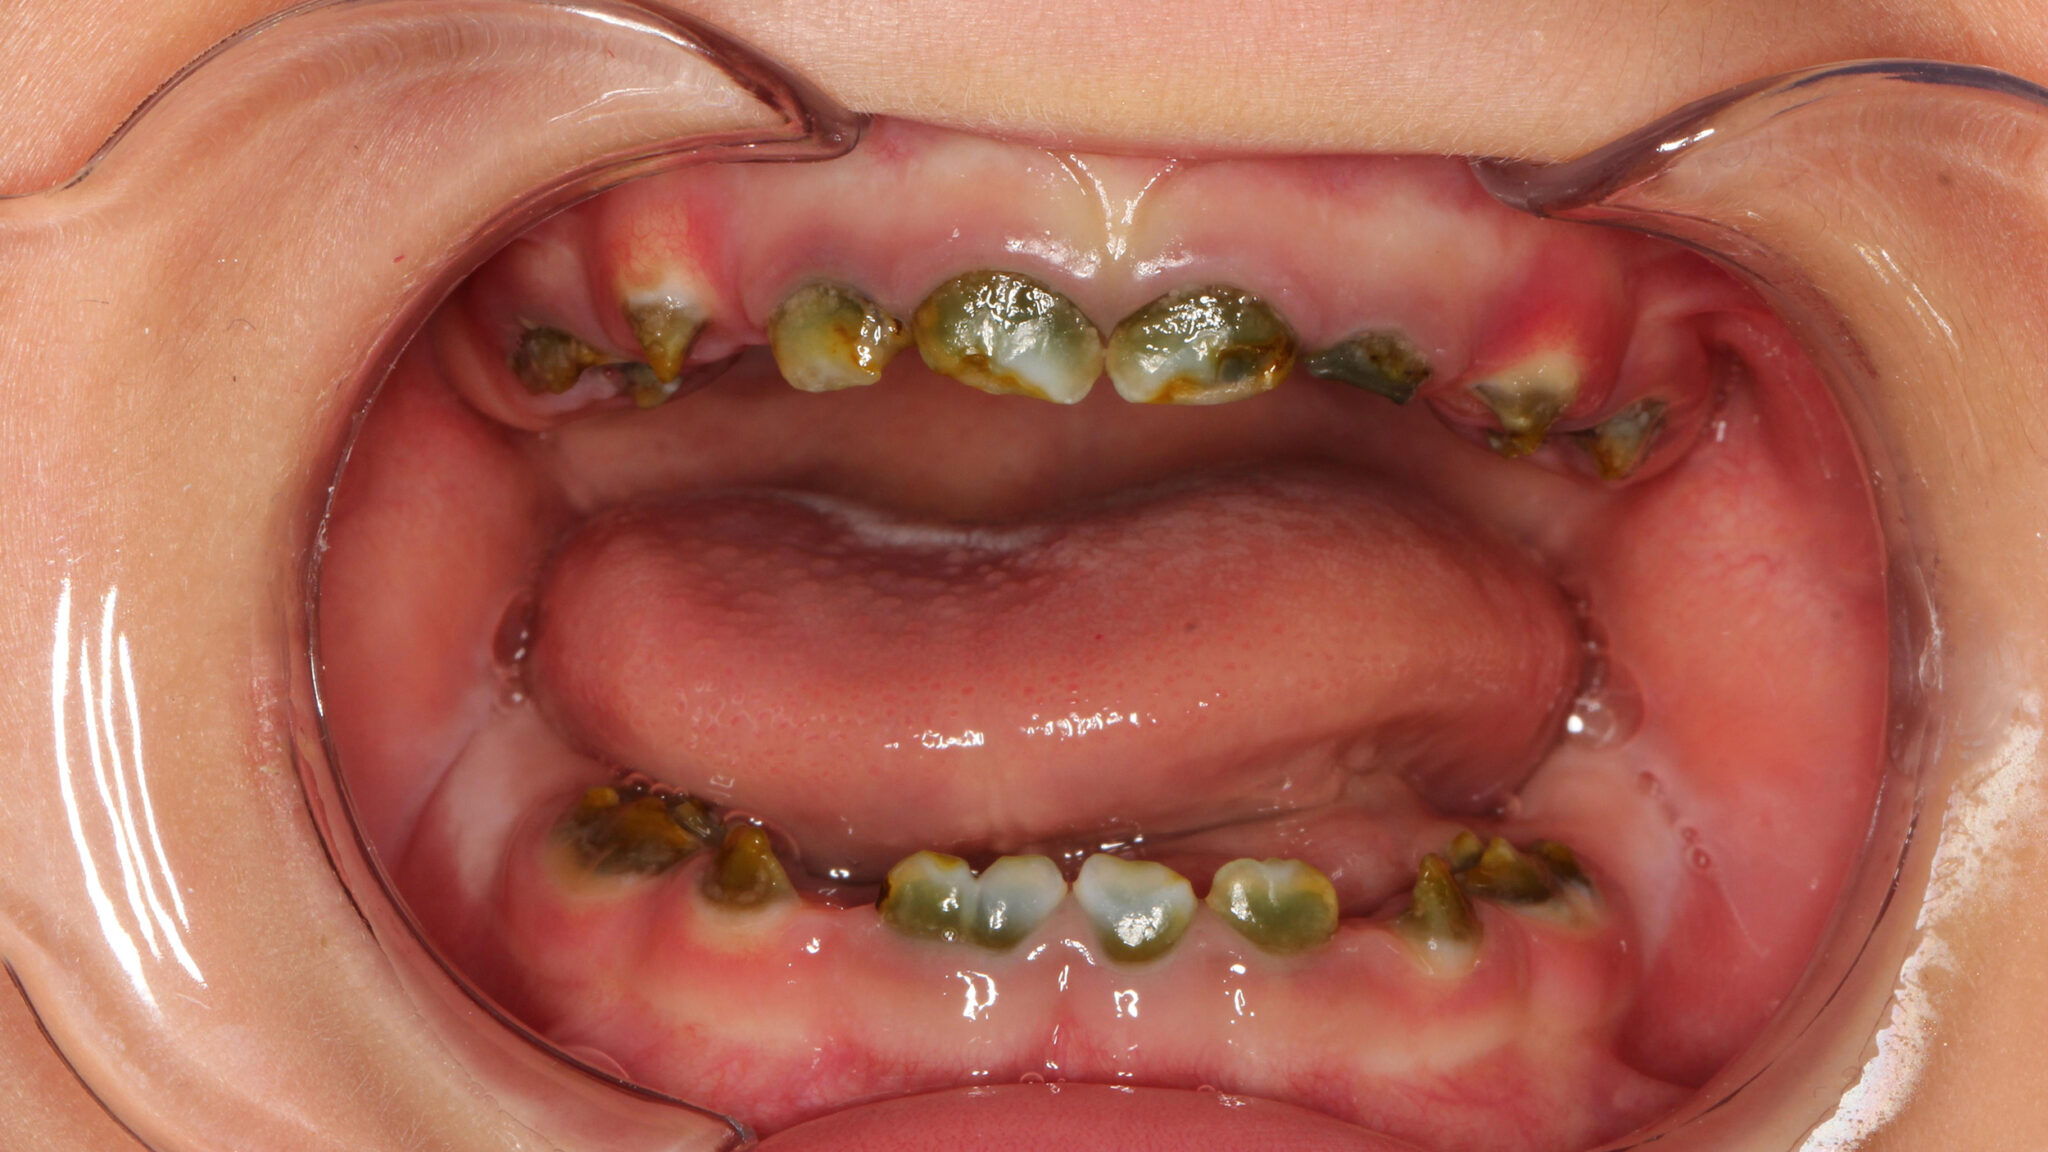

Green Teeth? The Many Shades of Congenital Syphilis

Figure2 alternate text for this image

It is a disease that you will learn about in dental school, but rarely see in actual practice. And given the many, varied features of congenital syphilis, when you do encounter your first case, you may need to review this condition and its presentation. Syphilis, generally, is on the rise in Canada. Between 2005 and … Read more